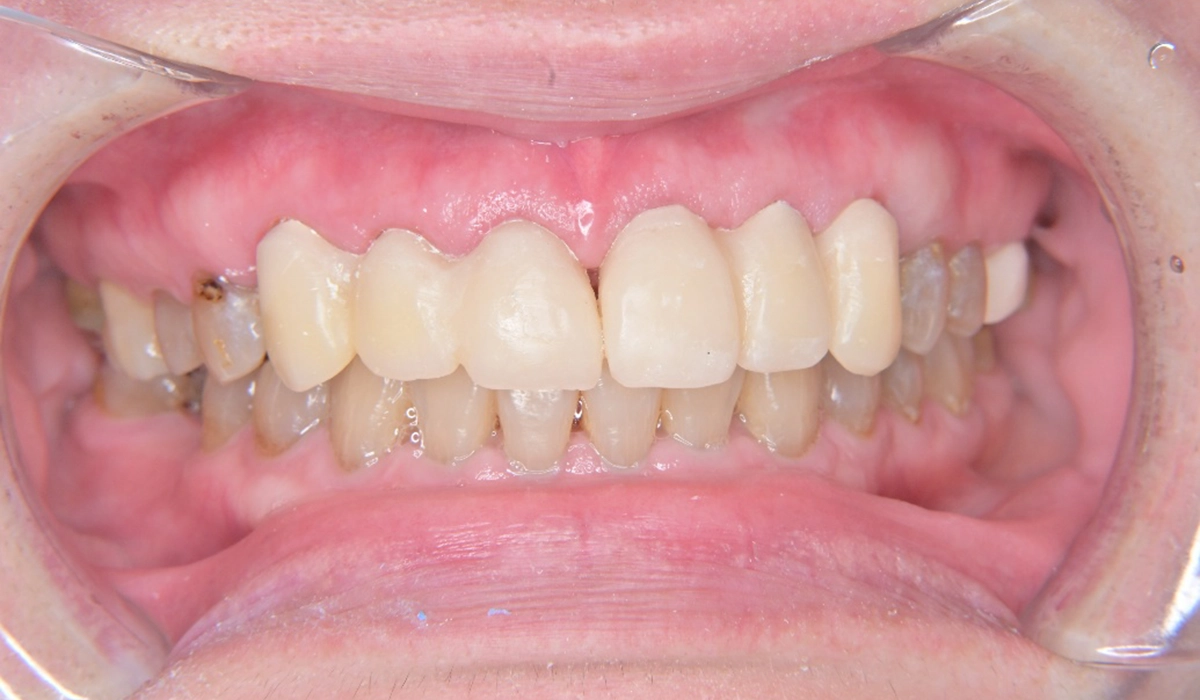

こちらが術前の口腔内写真になります。

問題点としては前歯部、臼歯部で進行したカリエスおよび前歯部歯肉増殖症、広範型慢性歯周炎StageⅡ GradeAが挙げられます。本症例では前歯部の審美性の回復について患者様との話し合いのうえセラミック修復による治療を選択しました。

治療のステップとして全顎的な歯周環境の改善のための歯周基本治療、前歯部の歯周形成外科、前歯部カリエスに対する根管治療、前歯部プロビジョナルレストレーションによる歯肉形態修正、最終補綴の順で治療を進めていきました。